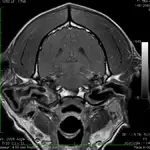

Imaging & Hearing Tests

Computed tomography (CT) (Figure 4) and magnetic resonance imaging (MRI) are preferable to radiography, which is an insensitive means of diagnosing otitis media. Brainstem auditory evoked response (BAER) testing is an accurate method of assessing hearing (Figure 5). When chronic irreversible change is present in the canals (calcification of the soft tissue) or middle ear (granulation tissue or bony change present in the bulla), or when the animal is deaf, medical therapy is inappropriate and a total ear canal ablation with bulla osteotomy should be performed.

Featured Image

FIGURE 4

Transverse plane T1-weighted postcontrast image in a 3-year-old dog with bilateral otitis media and otitis externa. The lining of the bullae and the walls of the external ear canals are enhanced, consistent with inflammation and exudate in the bullae.